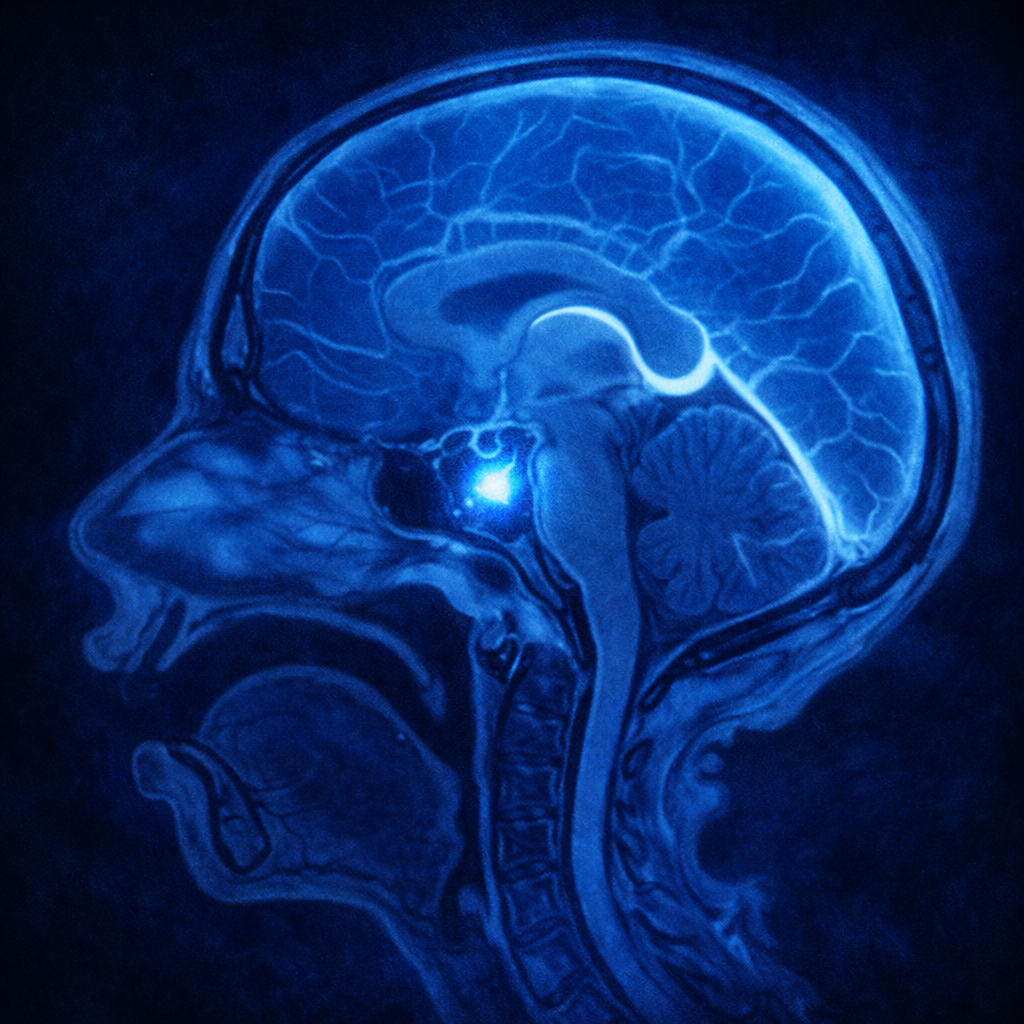

Cordoma de clivus

El cordoma de clivus es un tumor óseo maligno poco frecuente derivado de la notocorda embrionaria. Es un tumor de crecimiento lento con un comportamiento localmente agresivo.

Invade tejidos cercanos y puede comprimir estructuras vitales como el tronco encefálico, nervios craneales y vasos sanguíneos, lo que lo convierte en una condición compleja de tratar y tiende a recurrir, es por ello que la primera cirugía se convierte en la mejor opción, considerando el pronóstico del paciente.

- Resonancia magnética y tomografía computarizada para determinar el tamaño y extensión del tumor.